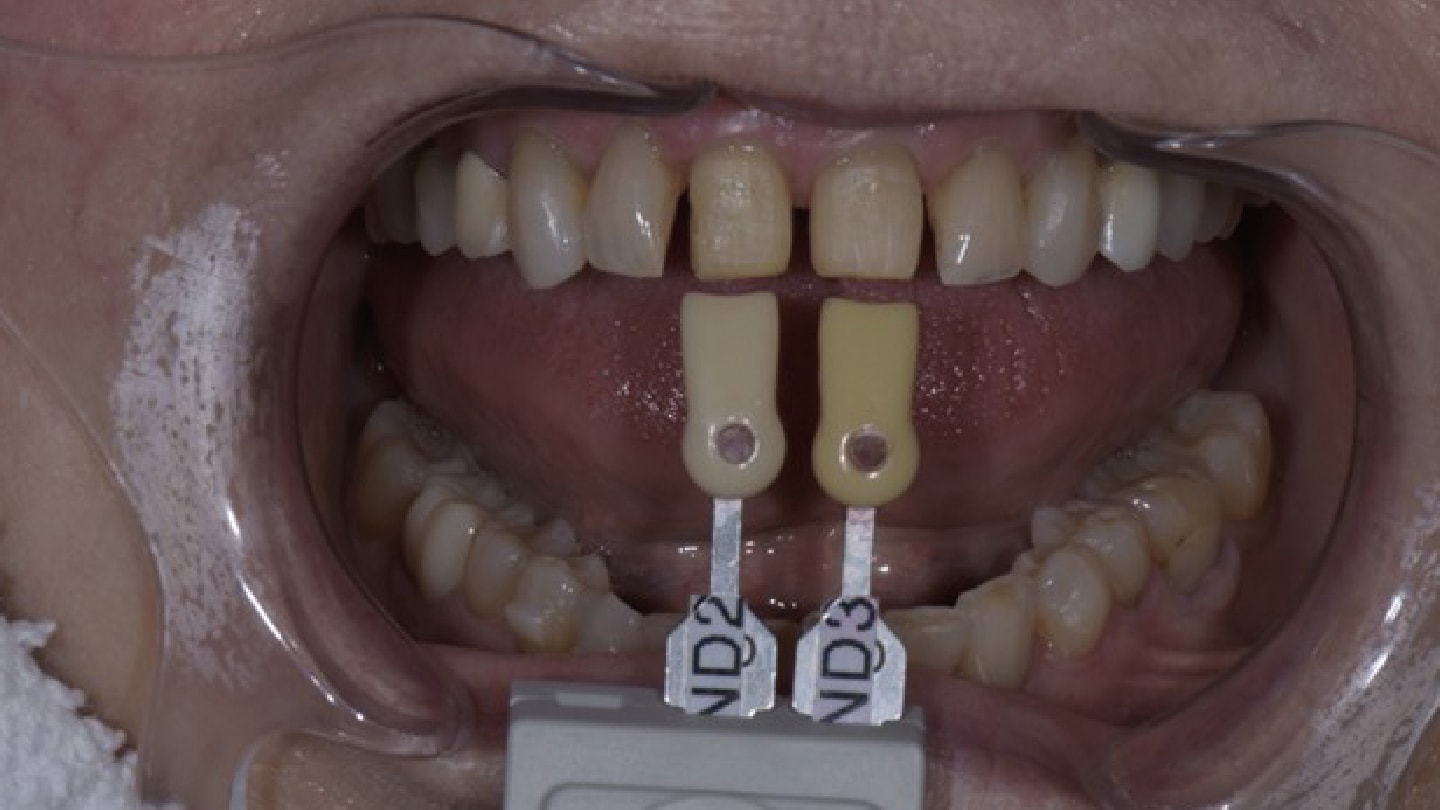

The patient was anesthetized and teeth Nos. 8 and 9 were prepared. Retracted polarized photos were taken of the prepared teeth with and without a stump shade guide for reference (Natural Shade Guide, Ivoclar) to aid in communicating the value of the stump shade and shade of adjacent teeth to the laboratory (Figure 14 through Figure 16) for fabrication of the veneers. The laboratory delivered a putty matrix of the patient-approved diagnostic waxup for chairside fabrication of temporary restorations. Using the shrink wrap technique,10 the preparations were spot etched for 15 seconds (Ultra-Etch, Ultradent Products Inc.) and rinsed and then a self-bonding agent applied (All-Bond Universal, BISCO) and cured (Valo X, Utradent Products Inc.). A self-curing bis-acryl composite temporary material (ExperTemp A1, Ultradent Products Inc.) was injected into the putty matrix and the putty matrix inserted into the patient’s mouth. The margins were trimmed with the embrasure between Nos. 8 and 9 slightly exaggerated to allow space for the papilla to drop down and close the space prior to seating the final restorations. After one week, the patient approved the provisional restorations, and a full complement of photos of the temporized patient was taken to communicate with the laboratory (Figure 17 and Figure 18).